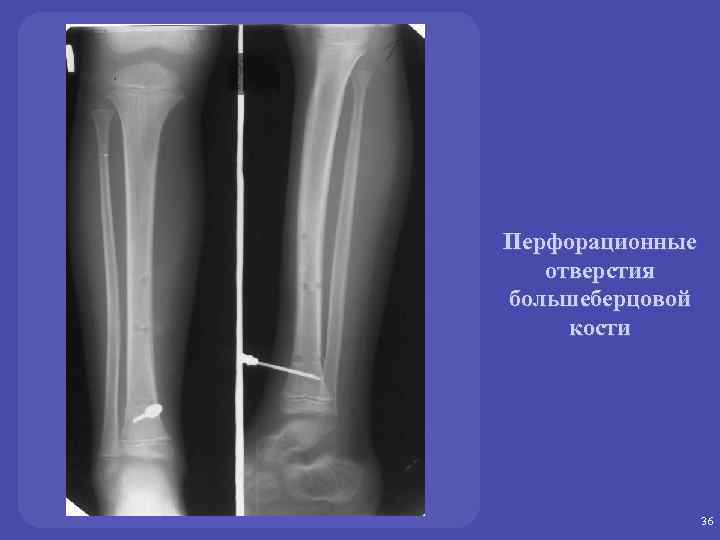

Перфорационные отверстия большеберцовой кости 36